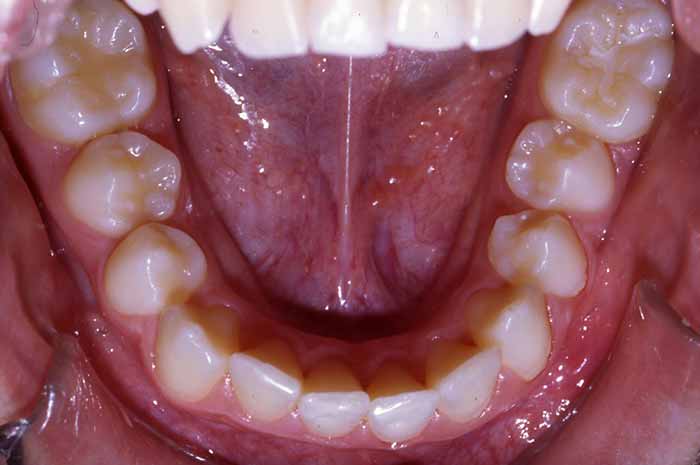

Problema:

Mordida cruzada anterior

Uno o varios incisivos superiores se situan por detrás de los inferiores, pudiendo alterar el correcto cierre de la boca.

Antes y Después